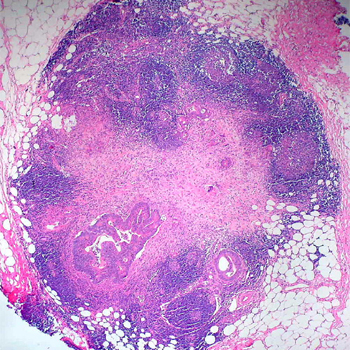

Descubren un nuevo síndrome genético que predispone al cáncer

Un nuevo síndrome causado por mutaciones bialélicas -las que se producen en ambas copias del gen, procedentes del padre y de la madre- en el gen FANCM predispone a la aparición de tumores y provoca rechazo a la quimioterapia. El gen, al contrario de lo que pensaban los científicos, no causa anemia de Fanconi. Los investigadores recomiendan modificar el seguimiento clínico de los pacientes con estas mutaciones.